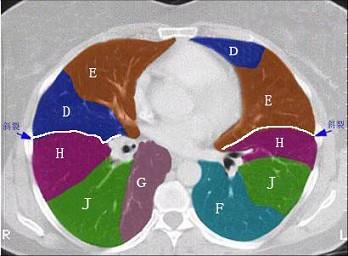

结合肺段模式(见图),选出右肺下叶的组成 ( )A、F+G+H+IB、F+G+H+I+JC、F+GD、F+G+HE、F

问题 结合肺段模式(见图),选出右肺下叶的组成 ( )

选项 A、F+G+H+I B、F+G+H+I+J C、F+G D、F+G+H E、F

答案 B